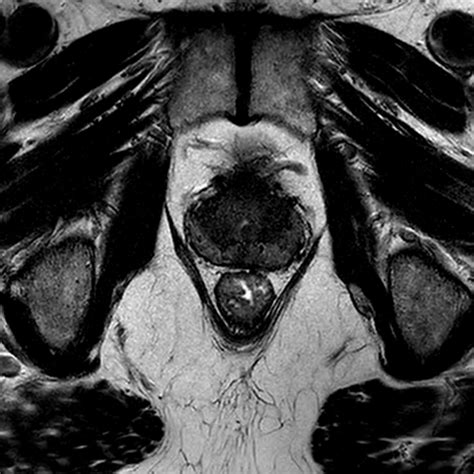

Before beginning prostate radiation treatment, you will undergo a planning process called "simulation." During this visit, your radiation oncologist will use CT scans or MRI imaging to map out the exact location of the prostate. You may receive small, permanent ink marks (tattoos) on your skin to help the treatment team ensure you are in the exact same position for every session.